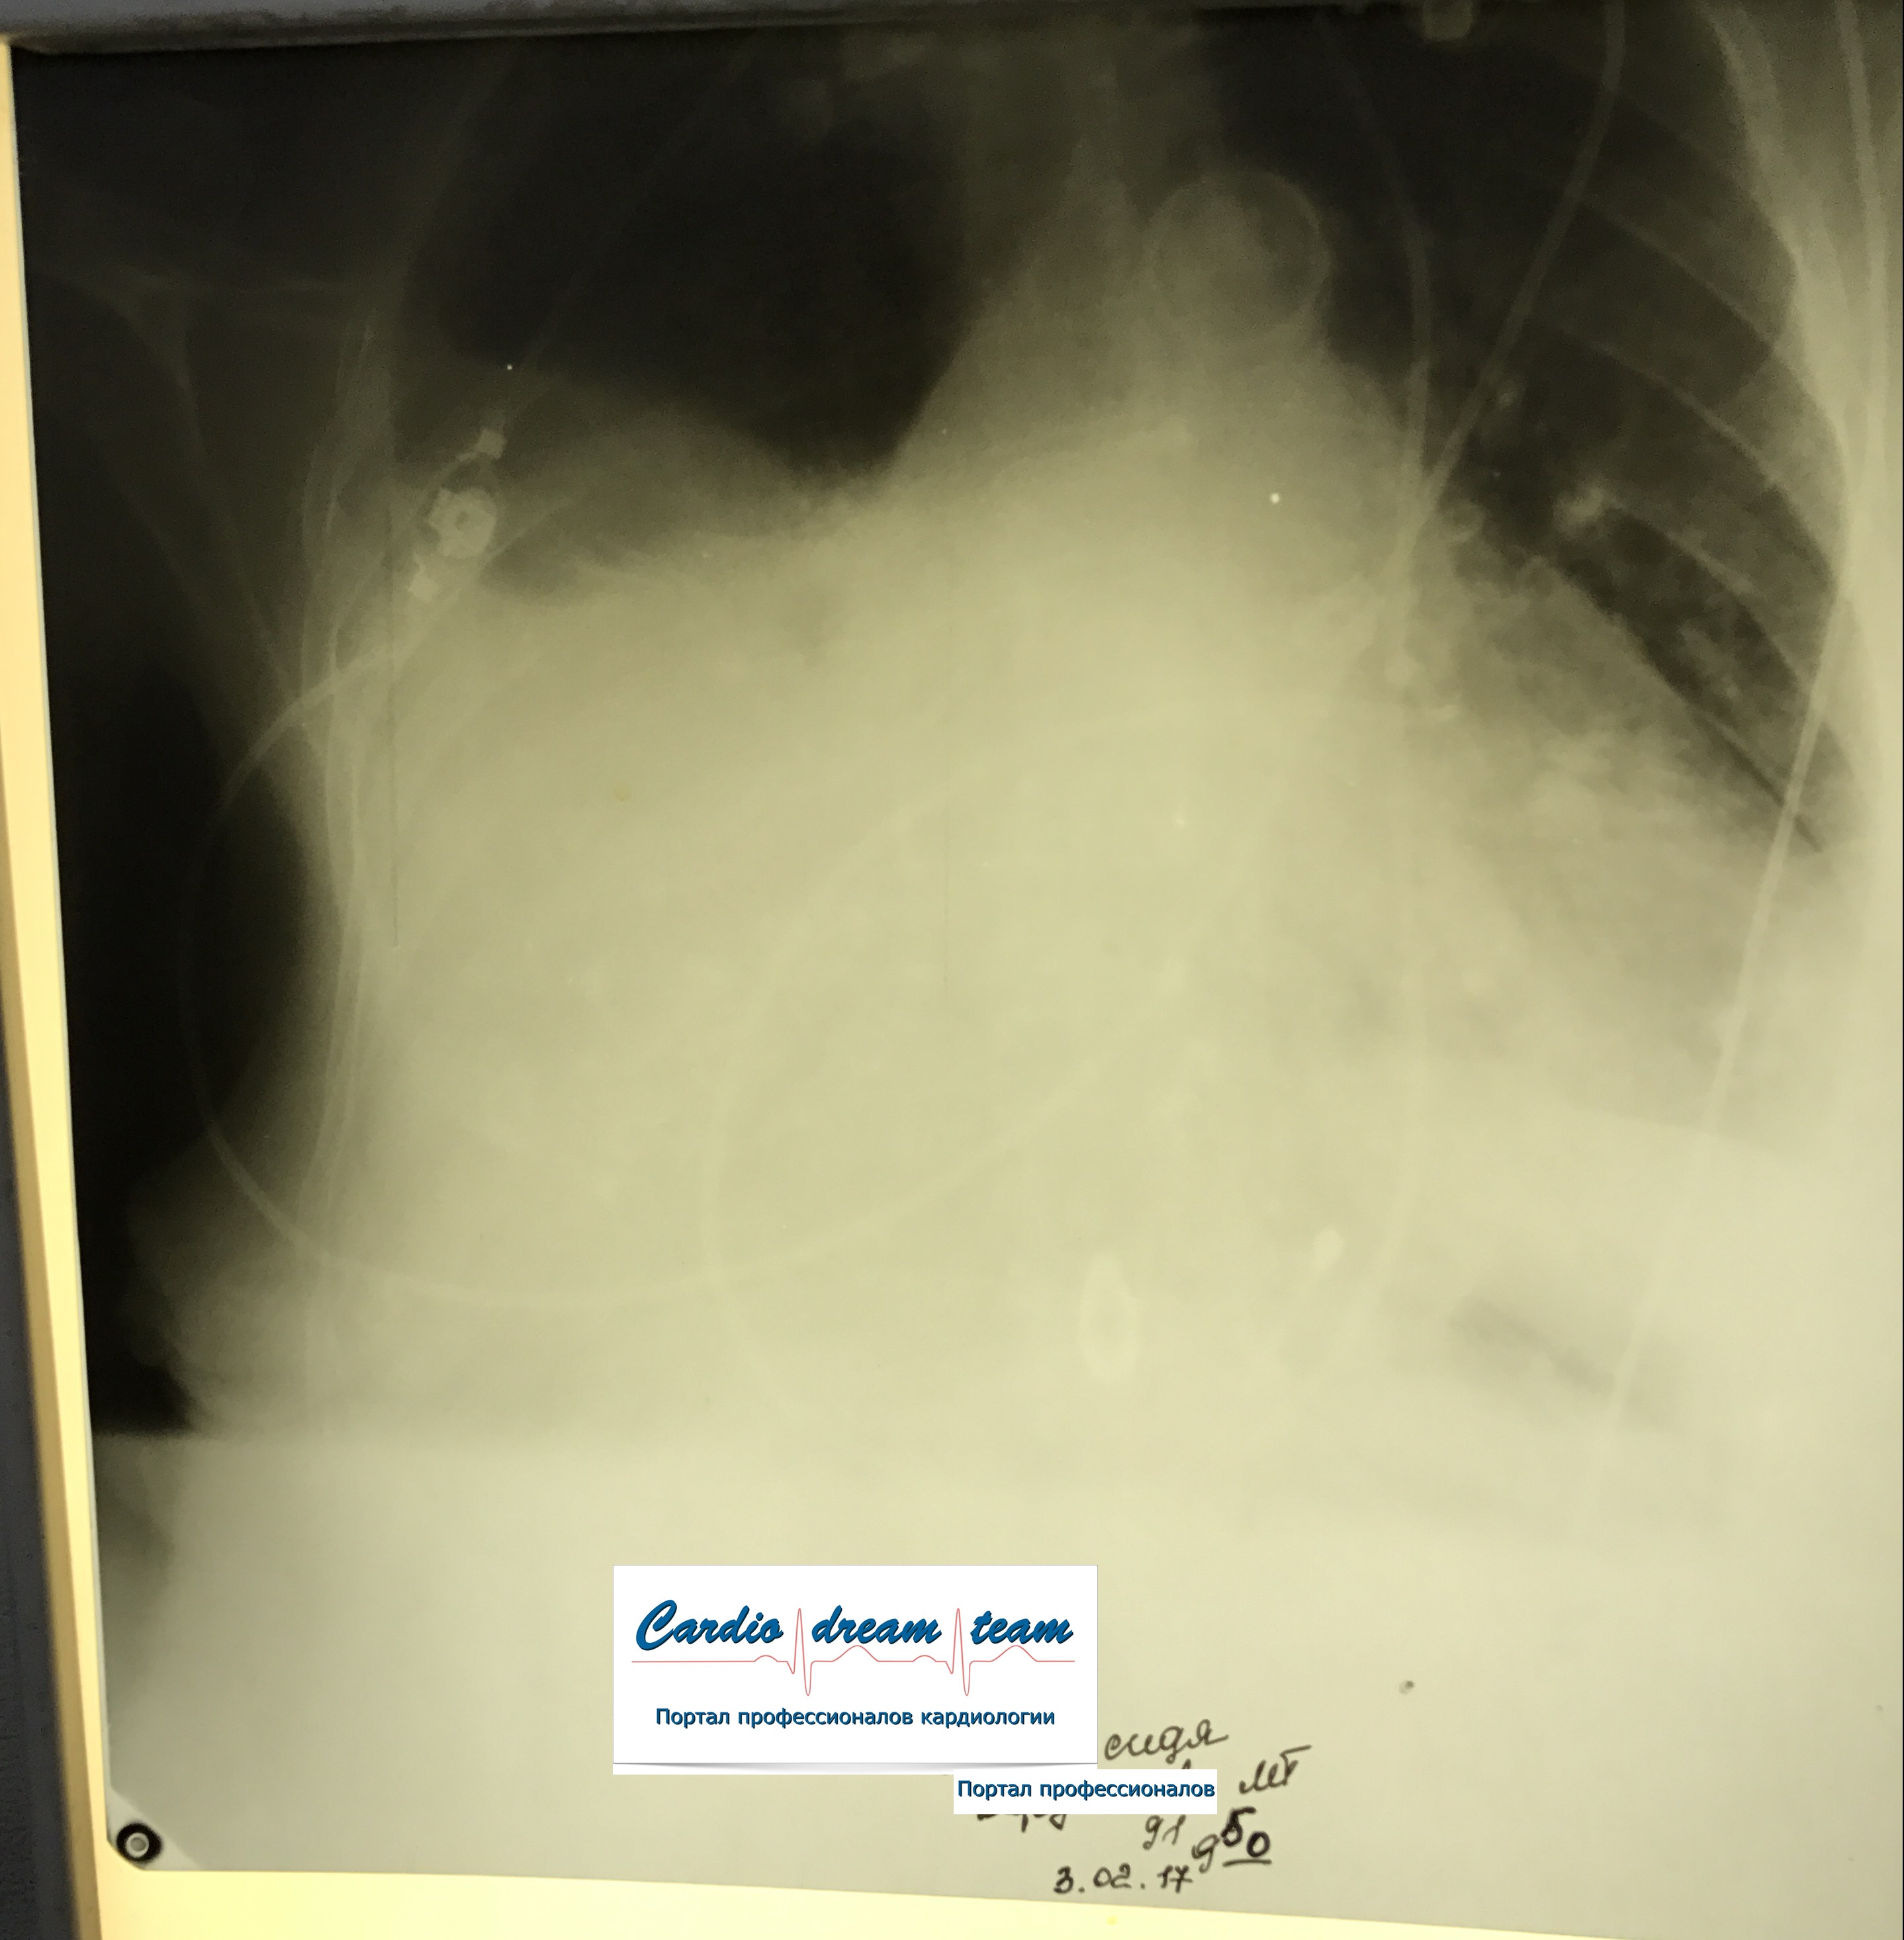

Гидроторакс. Серия снимков.

1 - лежа. Так делать не надо! Надо только сидя!

2 - сидя. Понятно, что гидроторакс за раз не победить

3 - удалено 1100.

4 - удалено ещё 1200. И диуретики все эти дни.